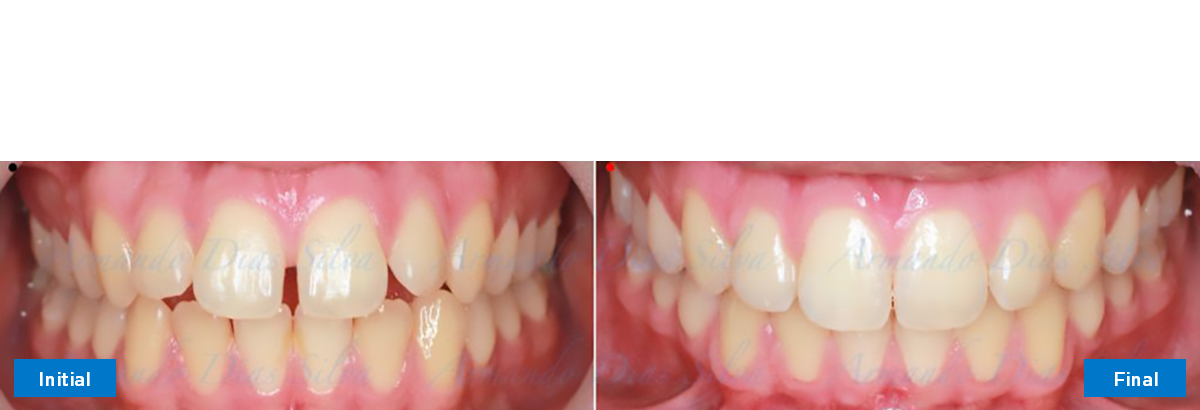

Principal queja del paciente: Protrusión del incisivo central y mordida abierta. El paciente rechaza la expansión del arco palatino (MARPE) y las extracciones.

Este paciente adolescente presenta molares de Clase II y no le gusta su mordida abierta ni lo protrusivos que son sus dientes frontales. Por sus fotografías faciales, parece que su mandíbula es retrognática o le falta volumen en la barbilla. El historial del paciente también indica que existe un problema funcional al no haber guía de los incisivos.

• Molares de clase II

• Diastema

• Incisivos superiores e inferiores proclinados

• Molares de clase I logrados con distalización y sin elásticos

• Sin expansión maxilar, respetando la envoltura periodontal